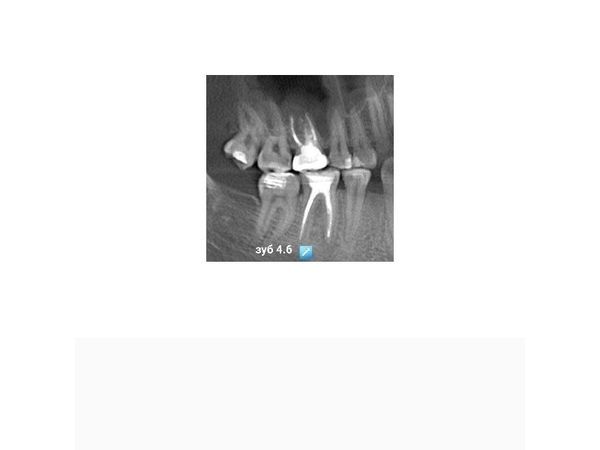

В июле 2021 года в стоматологическую клинику обратился 27-летний парень, чтобы решить вопрос по поводу удаления правого нижнего моляра (зуба 4.6).

В области мезиального корня зуба 4.6 отмечался обширный очаг разрушения кости, который распространялся от верхушки корней до места их соединения, тень пломбировочного материала в мезиальных корневых каналах нечёткая и неоднородная, располагалась пристеночно, доходила до половины и второй трети каналов (мезиального и дистального).

Хронический апикальный периодонтит зуба 1.6. Хронический периапикальный абсцесс зуба 4.6 со свищом.